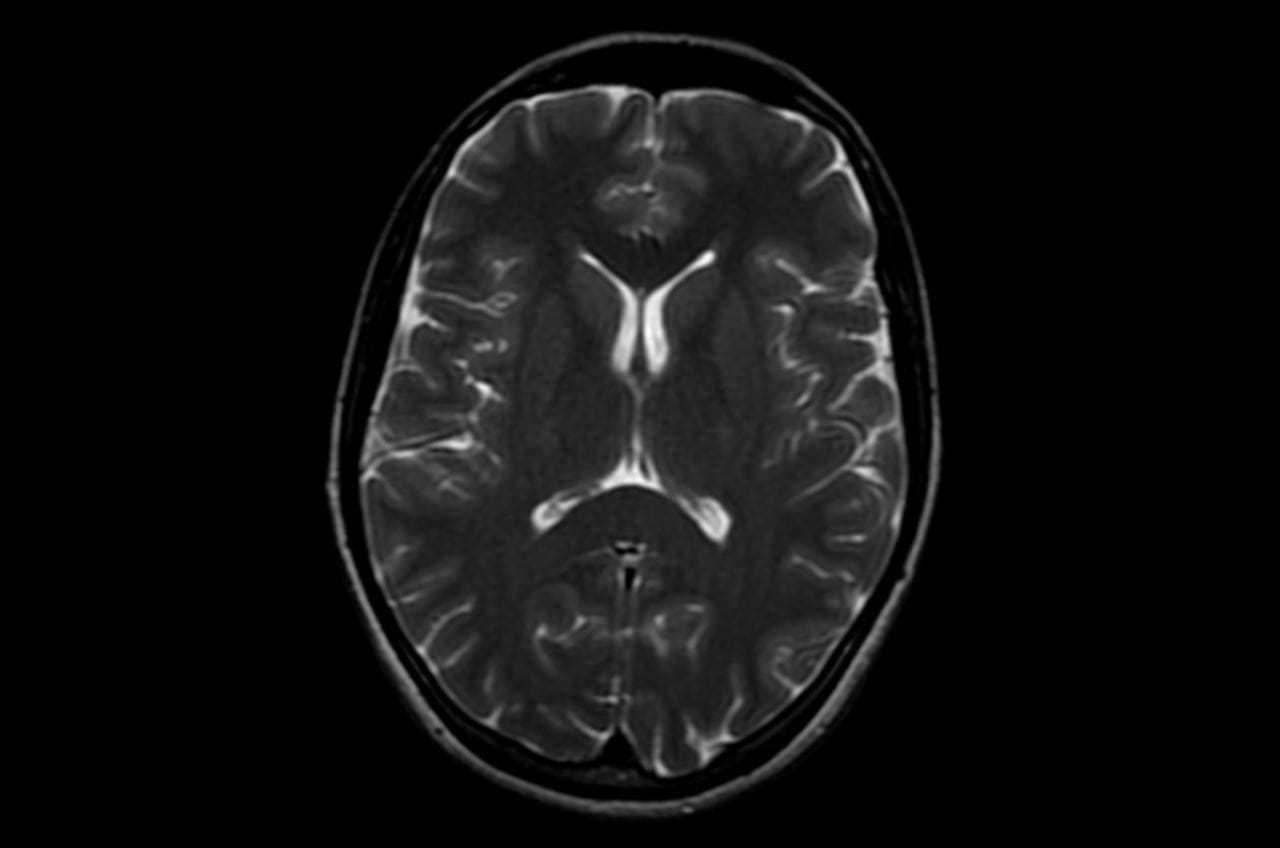

A scan of a human brain. Photo courtesy of Sean Novak.